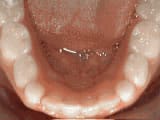

Spacing of teeth

Before

AfterThe patient was bothered by the spaces between his teeth. Braces closed the spaces and gave him an ideal bite in 24 months. Special glued-in retainers help keep the spaces closed.